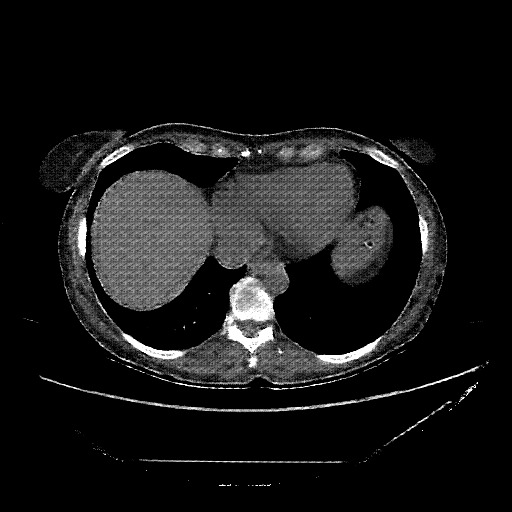

Reconstructed NATIVE CT scan (cycle consistency)

Full window (WL 1023.5, WW 4095 β†’ Low βˆ’1024, High +3071)

Mediastinum window (WL 40, WW 400 β†’ Low βˆ’160, High +240)